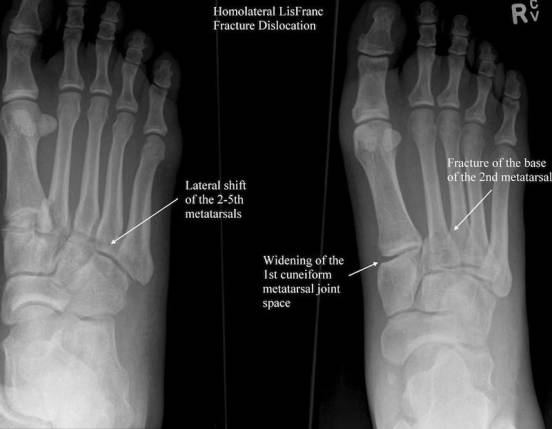

Lisfranc 损伤

Lisfranc关节即跖跗关节,跖跗关节复合体包括组成跖跗关节的骨、关节与韧带等全部结构。Lisfranc关节损伤即跖跗关节骨折脱位。